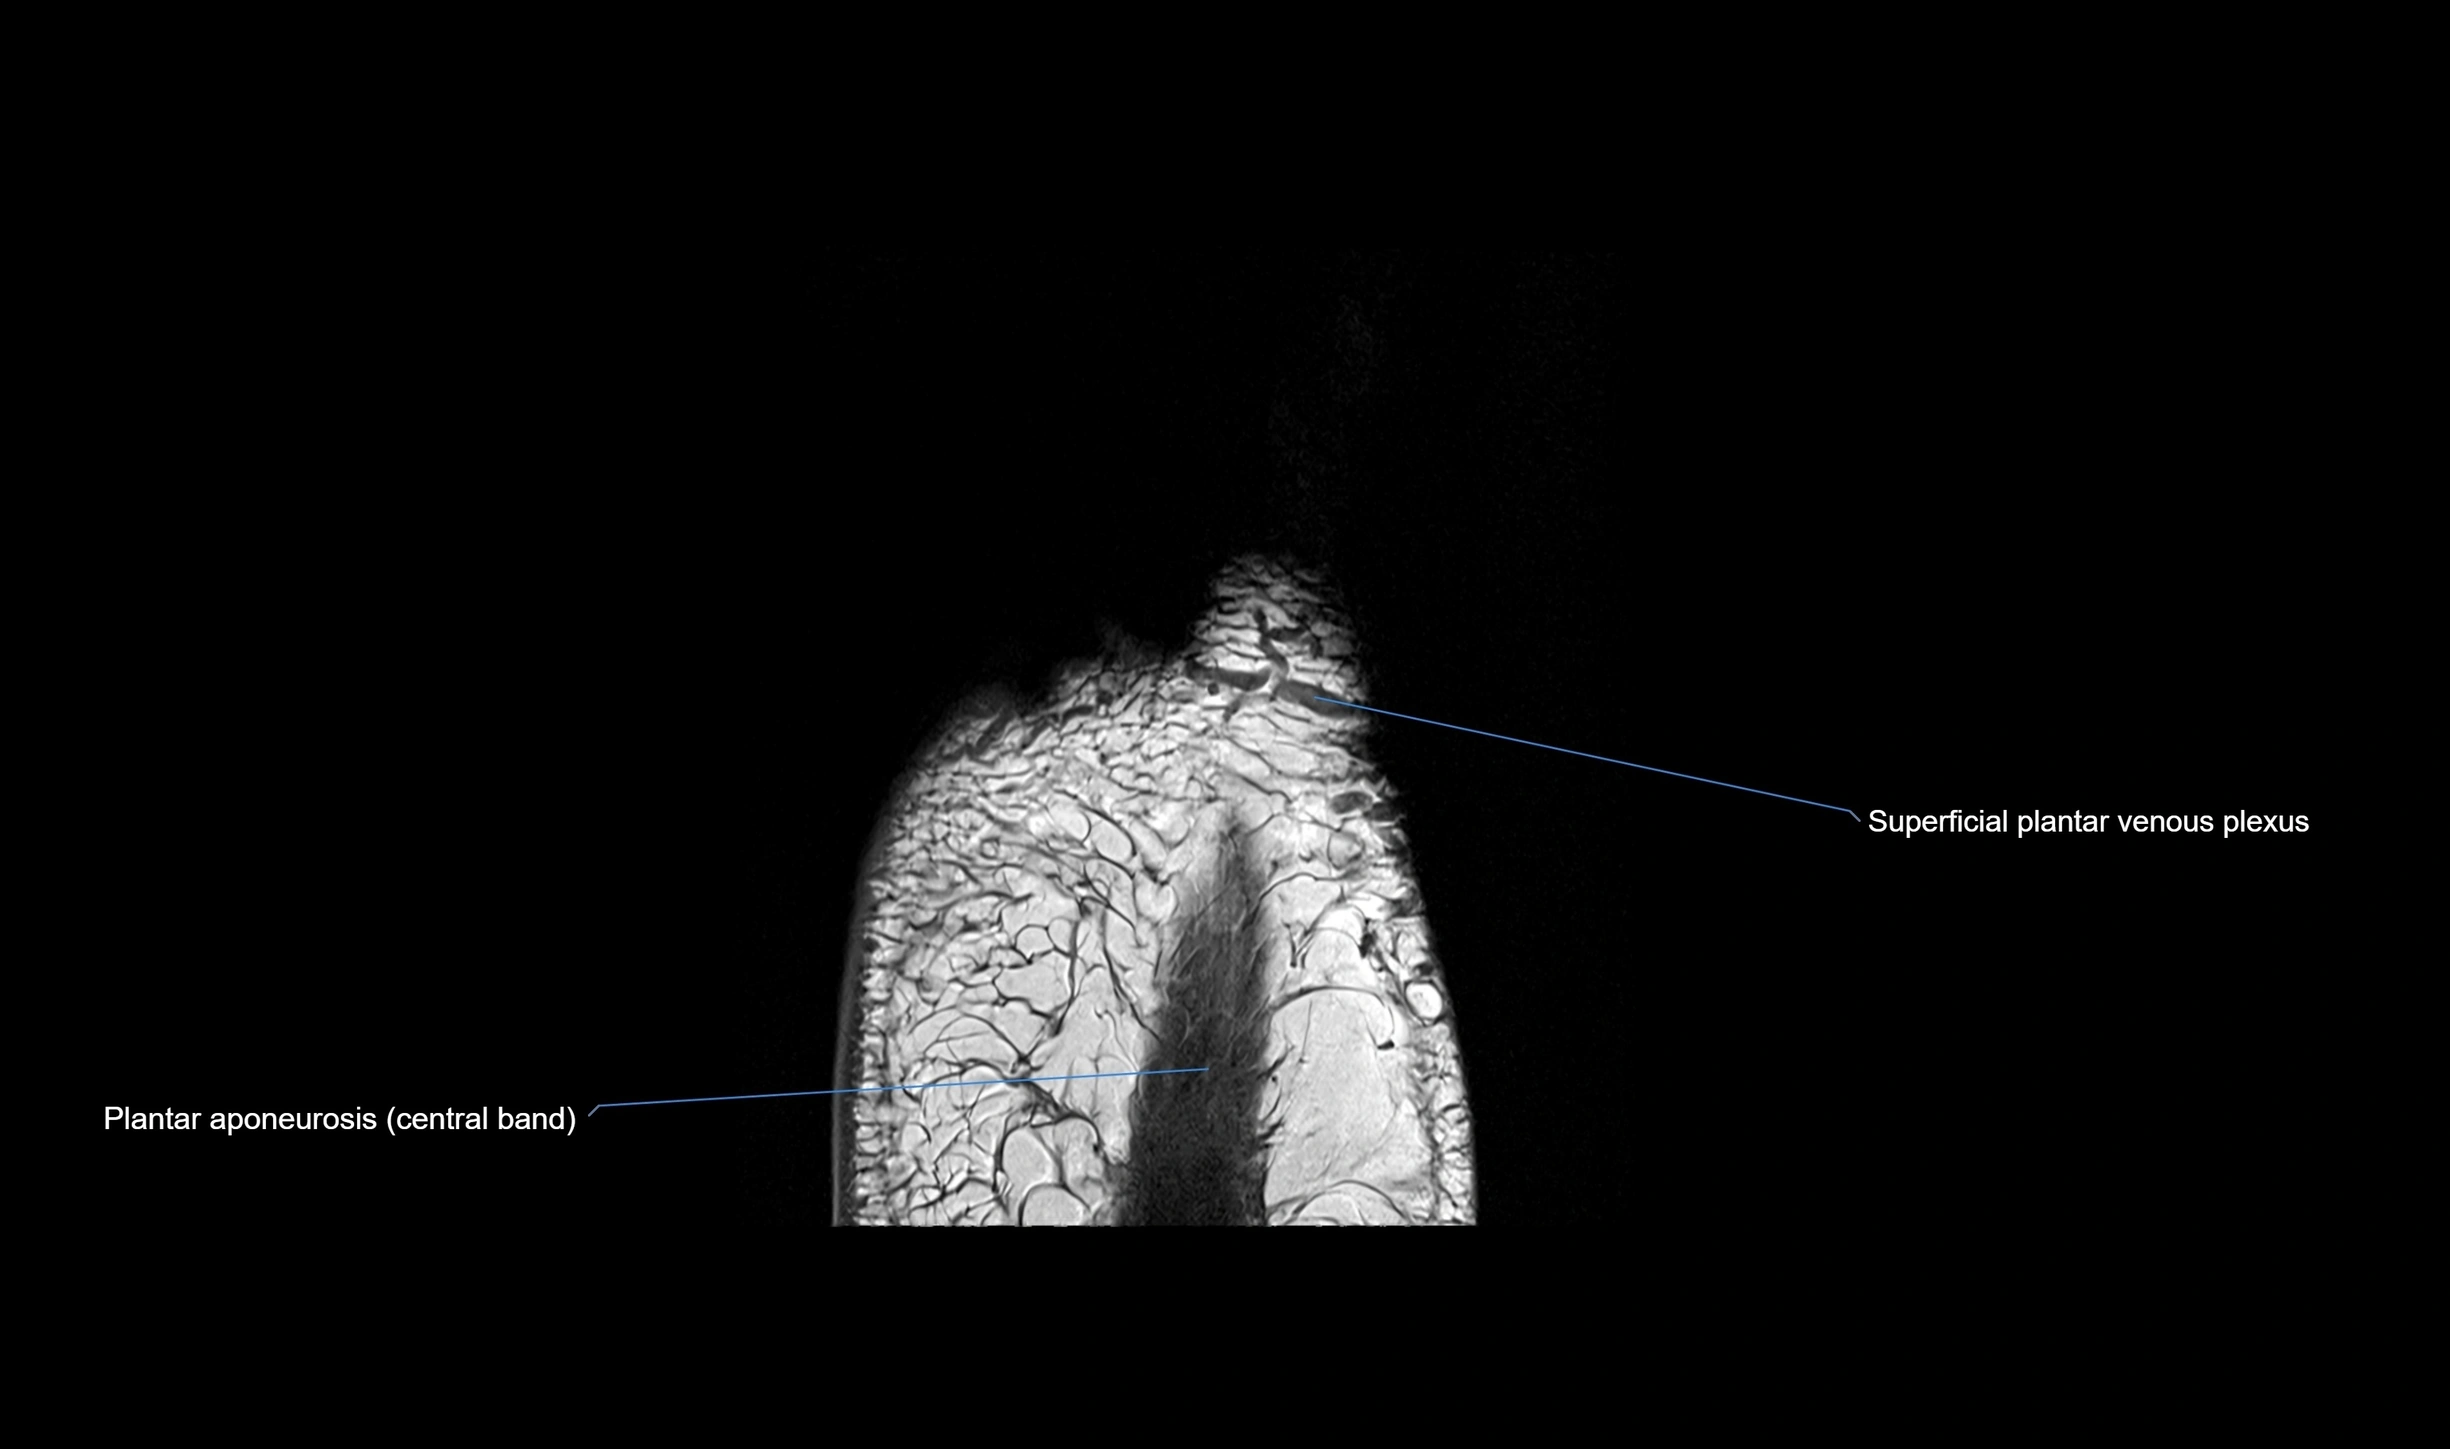

MRI image